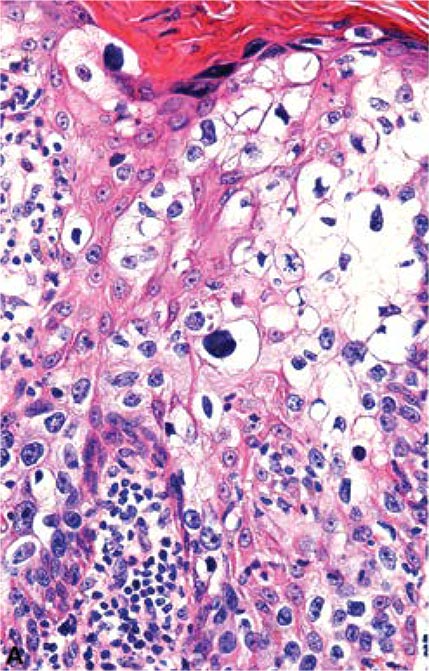

Dermatología gráfica